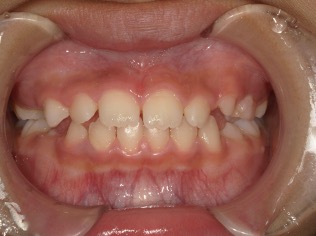

| 年齢・性別 | 女性 |

|---|---|

| 主訴 | 上の前歯が出ているのが気になる |

| 治療期間・回数 | 1年間 |

| 費用 | 330,000円(税込) |